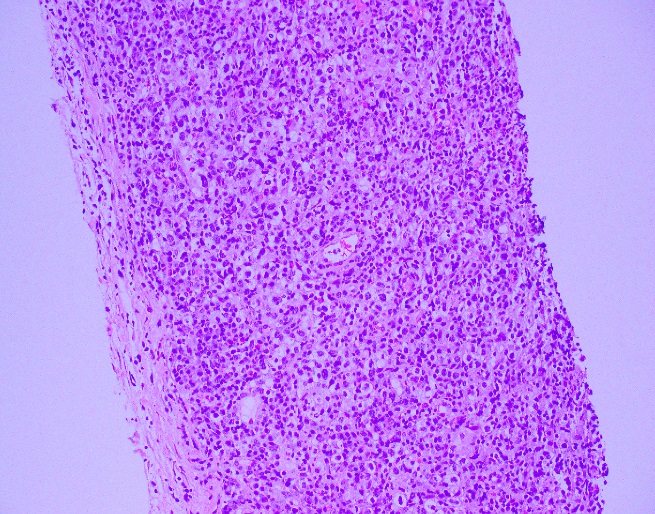

Histologically, the tumor consisted of spindle cells arranged in a fascicular pattern with intermittent whorled areas. The cells contained pleomorphic, hyperchromatic nuclei and intervening myxoid hypocellular areas. Mitotic figures were observed with sparse areas of necrosis and hemorrhage. S-100 was ordered on the prior biopsy of the mass, which was weakly positive. Based on these findings, the specimen was signed out as a malignant peripheral nerve sheath tumor.

Grossly, MPNST will present as a large, poorly defined, fleshy tumor that runs along a nerve and involves adjacent soft tissue. Often, these tumors will have areas of hemorrhage or necrosis and can track along the length of a nerve. Histologically, the tumors are composed of monomorphic spindle cells arranged in fascicles, palisades and whorls, with compact comma-shaped, wavy or buckled hyperchromatic nuclei with alternating hypocellular foci. (Image 3 and 4). Mitotic figures and necrosis are common, and although S-100 is considered the best marker for MPNST, there is a lack of specificity and sensitivity for immunohistochemical markers. Due to the lack of immunohistochemical markers and molecular findings, as well as the variability associated with the cells, it has traditionally been difficult to diagnose MPNST. The differential diagnosis includes fibrosarcoma, monophasic synovial sarcoma, desmoplastic melanoma, and pleomorphic liposarcoma. Goldblum et al put forth the idea that a diagnosis of MPNST can be made if the tumor falls into any one of the following three categories: